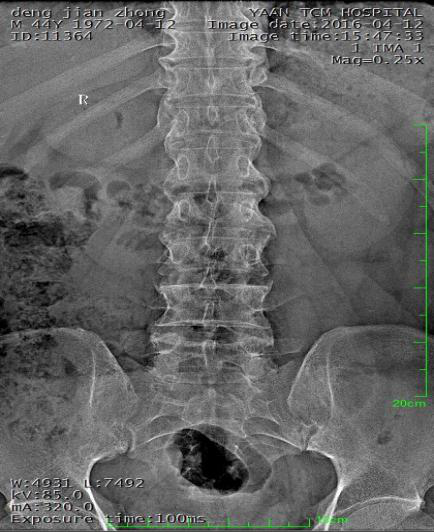

桡骨下端骨折

术前:

术后